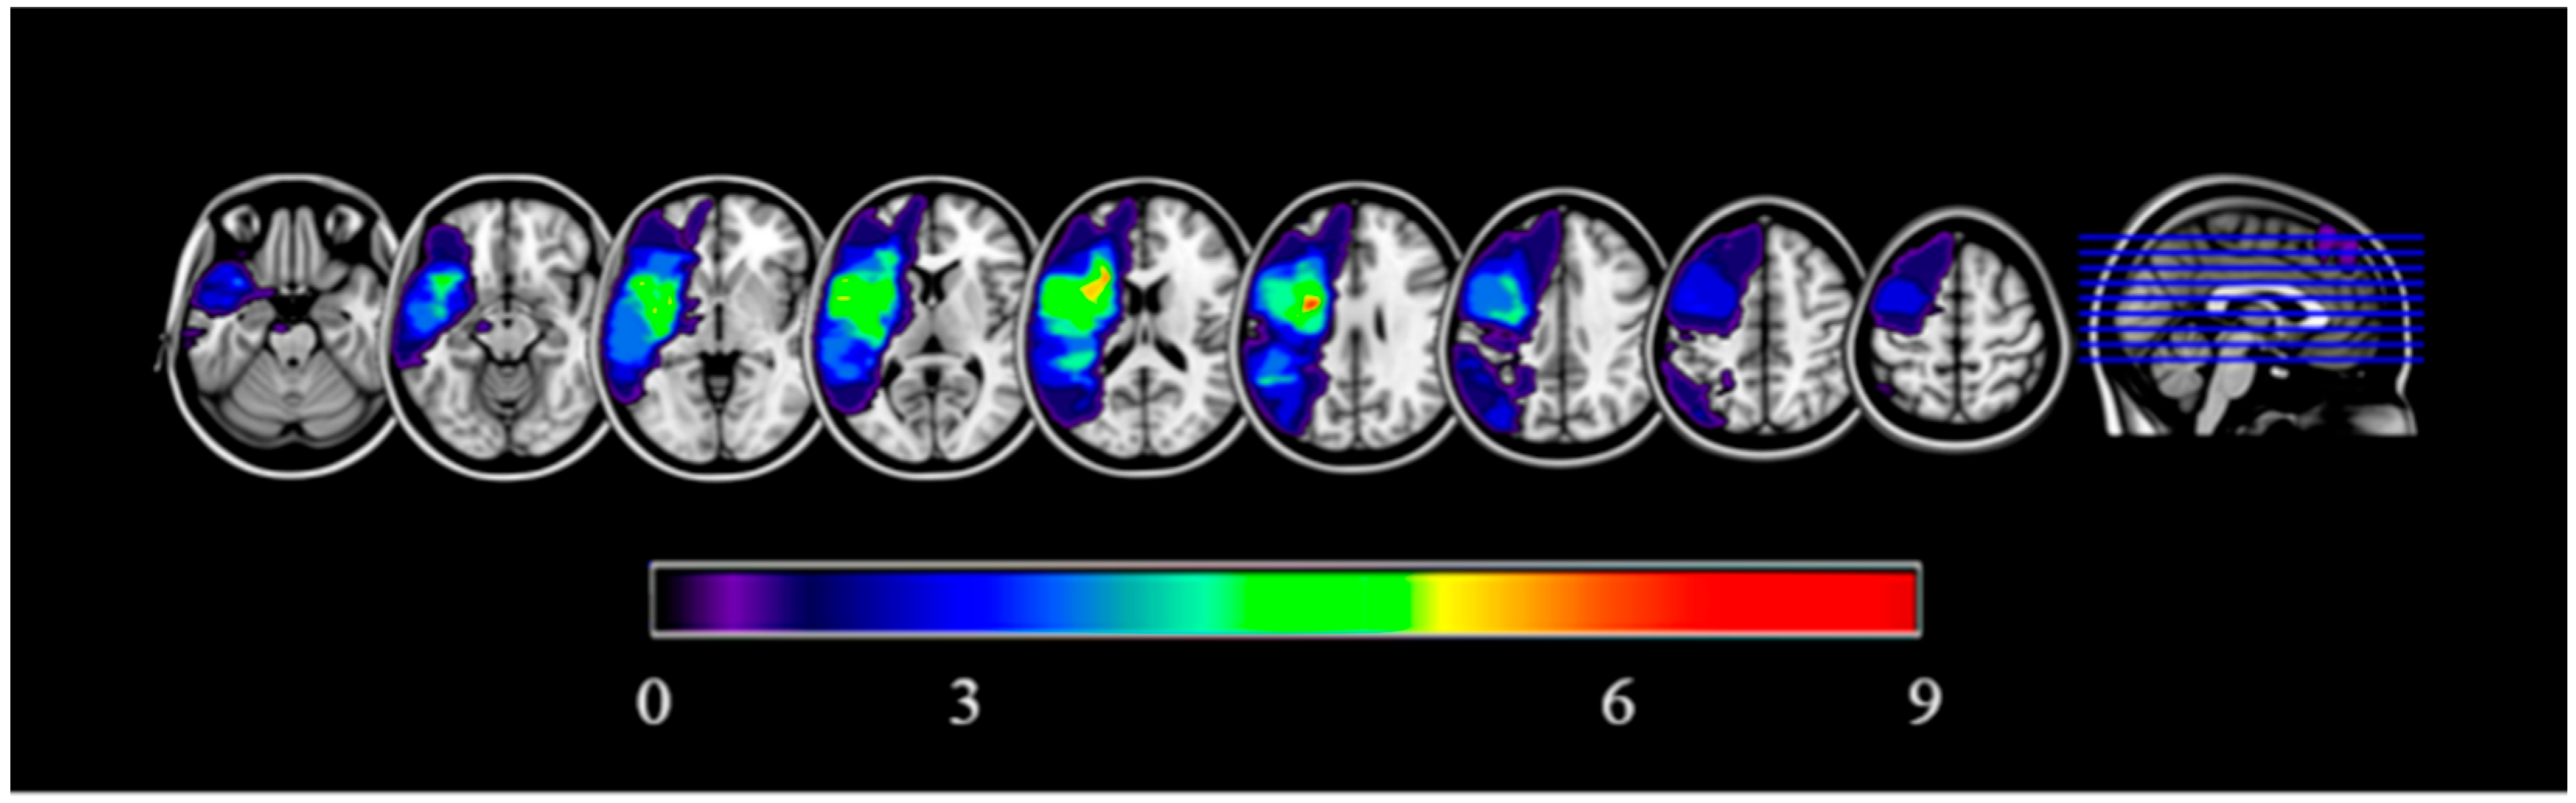

The sample consisted of 9 patients (4 females) with chronic post-stroke aphasia (whose ischemic episode, compatible with left middle cerebral artery affection, had occurred at least 6 months before participating in the study). Exclusion criteria were prior history of seizures or epilepsy, current use of anticonvulsant medications, history of cardiovascular or respiratory disease or other severe medical conditions, pre-existing dependency before stroke, contraindications for magnetic resonance imaging (e.g., metallic implants, pregnancy, claustrophobia), peripheral neuropathy or chronic pain disorders, lack of informed consent, high suicide risk, electroconvulsive therapy within the preceding six months, age over 85 years, and absence of naming errors according to the Boston Naming Test. Figure 1 illustrates the common lesion sites of the participants included in this work. The mean age was 60 years (SD = 14.86), and the years of education were 17 (SD = 4.74). Sociodemographic data, type of aphasia, and main lesion locations for each participant can be found in Table 1.

Figure 1. Participant’s common lesion site. Left hemisphere is presented on the left side for each axial section. Cold colors represent voxels that correspond to damaged areas in a smaller number of participants (e.g., dark purple = 1 participant with a lesion involving those particular voxels). Hot colors represent those voxels corresponding areas in a larger number of participants (e.g., red = 9 participants with a lesion involving those particular voxels). For presentation purposes, a slight smoothing was applied on the image (3 mm FWHM).